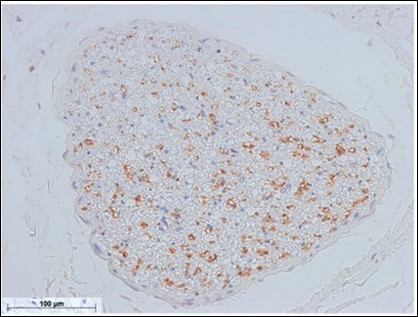

Figure 5.Sympathetic nerve fibers of the optic nerve (anterior facial nerve: TH staining) Bar = 100um

Sympathetic nerve fibers of the optic nerve (anterior facial nerve: TH staining) Bar = 100um

Based on the results obtained in this study, the mental nerve and the marginal mandibular branch of the facial nerve are completely fused at the perineurium. Most nerve diagrams indicate that the mental nerve is only a sensory nerve, and that the marginal mandibular branch of the facial nerve is a pure motor nerve. However, we found that there is a need for autonomic nerves to be present in the lower face region, where there are salivary glands and sweat glands, including the lower lip and chin (the regions of these nerves). Hence, we aimed to determine where these nerves originate. In the present study, we observed that the vasomotor nerve of the facial artery branched off from the buccal branch and the marginal mandibular branch of the facial nerve (Figure 2※), and we identified the fact that there are sympathetic and parasympathetic fibers in the facial nerve. This was also confirmed micro-anatomically. Figure 5 shows a cross-section of the optic nerve, and Figure 6 shows a cross-section of the mental foramen region of the mandibular nerve. Tyrosine hydroxylase immunostaining stained the sympathetic nerves (provided by lecturer Masahito Yamamoto of the Department of Anatomy, Tokyo Dental College). The trigeminal nerve includes sympathetic fibers, and when the two sections are compared, the optic nerve has a substantial number of such fibers, whereas the mandibular nerve has very few. Matsubayashi 10 wrote extensively on this issue. It is known that the trigeminal nerve, which is the great auricular nerve, auriculotemporal nerve, and zygomatic branch of the facial nerve, consists of cutaneous nerves of the face and sympathetic nerve fibers, although there are few sympathetic nerve fibers in the maxillary nerve or mandibular nerve.